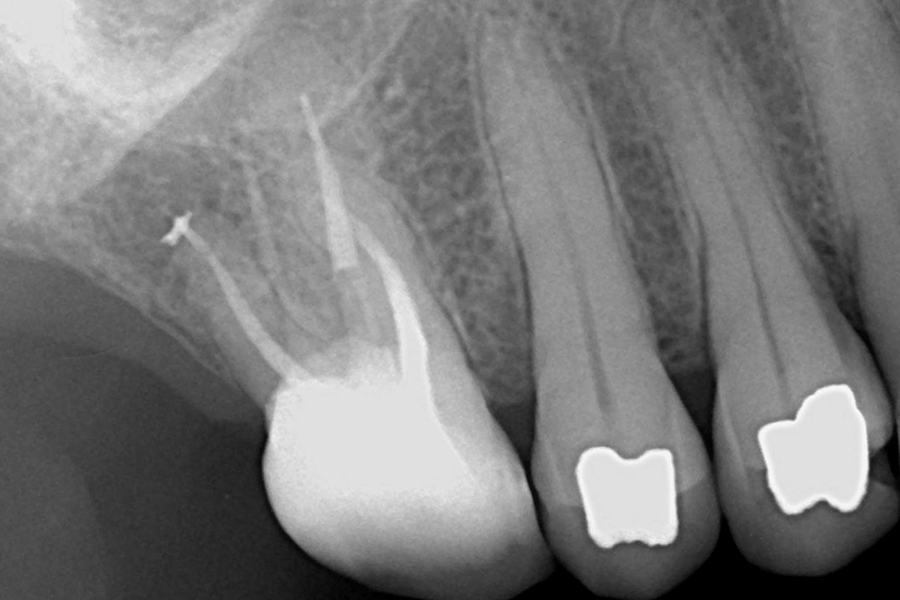

تنها راه نجات پالپ آسیبدیدهای که دچار عفونت شده است، عصب کشی یا روت کانال بهشمار میآید. جهت انجام عصب کشی، ابتدا دندانپزشک بررسیهای لازم را از دندان آسیبدیده انجام میدهد و با دیدن تصویر اشعه ایکس دندان عفونی شده، درمان نهایی و اثربخش را به شما پیشنهاد میدهد. در پروسه درمان عصب کشی، پالپهای عفونی و ملتهب از داخل دندان خارج میشوند تا مشکل به صورت کامل برطرف شود.

در ابتدا دندانپزشک یا متخصص درمان ریشه، دندان آسیبدیده را به صورت کامل معاینه مینماید، سپس وضیعت دندان را با کمک عکس رادیولوژی بررسی میکند تا میزان عفونت و پوسیدگی را تشخیص دهد. به جهت کم شدن درد و ناراحتی بیمار در هنگام درمان، داروی بیحسی موضعی به ناحیه درمان تزریق میکند. دندانپزشک در این مرحله میلهای پلاستیکی به منظور خارج شدن آب و ترشحات، داخل دهان قرار میدهد. سپس متخصص با کمک وسایلی مانند «دریل» و «فویل» پوسیدگیهای روی دندان را برمیدارد و عاج دندان را برای رسیدن به پالپ باز میکند. دندانپزشک با کمک ابزاری کوچک عفونتها را نیز خارج مینماید.

میدانید یکی از ملزومات درمان عصب کشی، داشتن تصویر اشعه ایکس از دندان آسیبدیده است. شما با مراجعه به کلینیک میتوانید پس از عکس برداری از دندان آسیبدیدهتان، در بخش مربوط به عصب کشی تحت درمان قرار بگیرید. درمان روت کانال در کلینیک لبخند درمان توسط متخصصین ریشه درمانی و با استفاده از تجهیزات روز و باکیفیتترین مواد انجام میگیرد. شما با مراجعه به کلینیک ما از خدمات تخصصی مجموعه میتوانید برخوردار شوید.